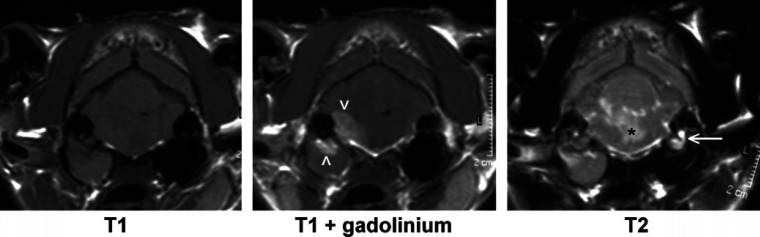

Fig 2.

Example of images from a cat with toxoplasmosis showing multifocal lesions. The initial T1-weighted image (left) appears normal, but hyperintense foci (arrowheads) are visible affecting the cerebrum after gadolinium contrast medium administration. The T2-weighted image shows hyperintense foci, representing oedema, in the same sites.

Extracranial lesions were identified in three cats. Two cats had material in the tympanic cavity compatible with otitis media; one of these had no intracranial signs, but the other had a focal lesion affecting the metencephalon and adjacent meninges and a diagnosis of bacterial meningitis. It is likely that the otitis and meningoencephalitis were related in this cat (Fig 4). The remaining cat had thickening of the lining of the frontal sinuses compatible with sinusitis and no intracranial signs.

Fig 4.

MR images of a cat with otitis externa, media and interna and associated meningoencephalitis. Isoechoic material fills the right bulla and horizontal auditory canal. Focal enhancement after gadolinium contrast medium administration is visible affecting the lining and the dorsal aspect of the right bulla and adjacent pons (arrowheads). In the T2-weighted image there is evidence of oedema affecting the pons (*) and a lack of a signal from the right inner ear. (The normal signal from perilymph in the left inner ear is arrowed.)